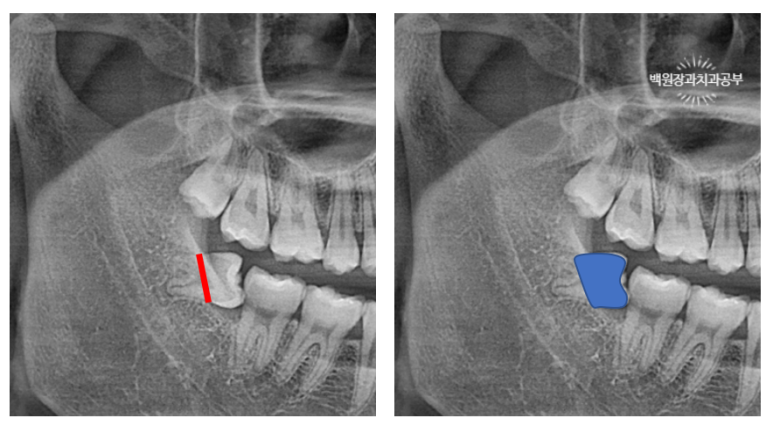

왼쪽의 파노라마 엑스레이에 그려진 빨간 선대로 치아를 나눌 예정입니다.

따라서 오른쪽 에 표시된 파란색 치아부분이 보일만큼 잇몸을 젖히고 잇몸뼈 삭제를 하는 것이죠.

계획했던대로 치아를 나눠줍니다.